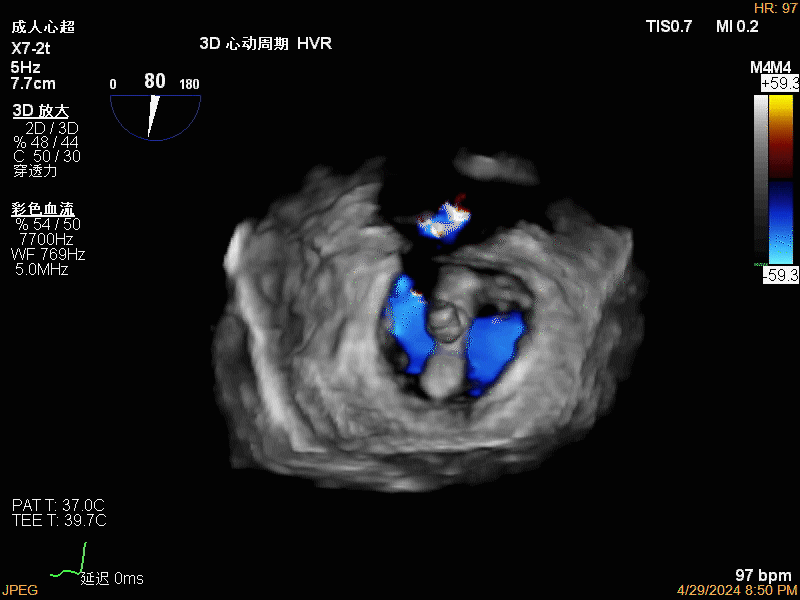

团队在反流最严重的2区精准植入1枚二尖瓣夹,即刻反流下降至微量,血压即刻上升20mmHg,跨瓣压差不升反降,由3mmHg降至2mmHg,改善效果明显,手术仅耗时一个半小时。 这是时隔四年继2020年指导开展区域内首例TAVR(经导管主动脉瓣置换)手术之后,陈茂教授再次带领华西团队,指导开展内自同城区域首例TEER术。陈茂教授对四院心内科心超图像的采集、房间隔穿刺的技巧、手术流程细节的把握、团队的默契配合、术前术后的管理表示称赞,鼓励四院心内科再接再厉造福区域患者。 患者为71岁老年女性,反复出现心累、气促已经超过10年,10多年来心衰的症状逐渐加重,间隔时间越来越短,且近1个月来已经3次因心衰住院,本次住院前已经无法耐受缓慢步行、如厕等日常生活,BNP超过了3000ng/ml。心电图为房颤,心超示左心室明显增大(65mm),重度二尖瓣反流(4+,CarpentierI+IIIb型),射血分数仅为31%。前叶长度:2.27cm且瓣尖增厚,后叶长度:1.14cm且局部钙化,瓣口面积:4.08cm2,反流宽度:1.7cm。患者及家属均拒绝外科开胸手术。 难点: 1.食道超声下该患者房间隔较厚较韧,且粗测高度仅为4.0cm,对穿刺的位置和技巧有较高要求; 2.左心扩大,反流宽度约17mm,放一个夹子可能不能有效解决反流,如放两个夹子需side by side 平行放置,但放置两个夹子有术后狭窄的风险; 3.前后叶对合似有间隙,若选用长宽夹子,会增加瓣叶张力,有瓣叶撕裂的风险,若选用短宽夹子,其捕获瓣叶的难度将增加; 4.患者心功能极差,手术需稳、准、快,不能耐受任何并发症风险。 影像资料 房间隔穿刺